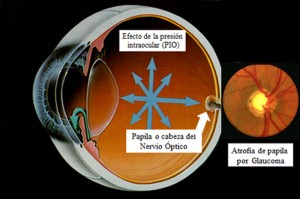

El objetivo de este estudio publicado en el número de abril de 2016 de la revista Journal of glaucoma es analizar el cambio en el astigmatismo corneal después realizar trabeculectomía.

Se incluyeron un total de 47 ojos. La media de la presión intraocular se redujo de 17,5 ± 5,4 mmHg en el preoperatorio a 9,8 ± 4,0 mmHg después de 6 meses. A los 6 meses 32 de 47 ojos mostraron un cambio en el astigmatismo a favor de la regla, con una diferencia media en el cilindro de 0,50 D.